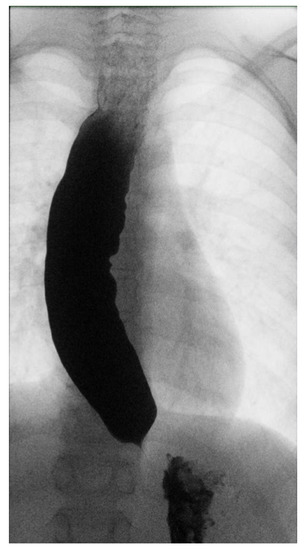

1. Case